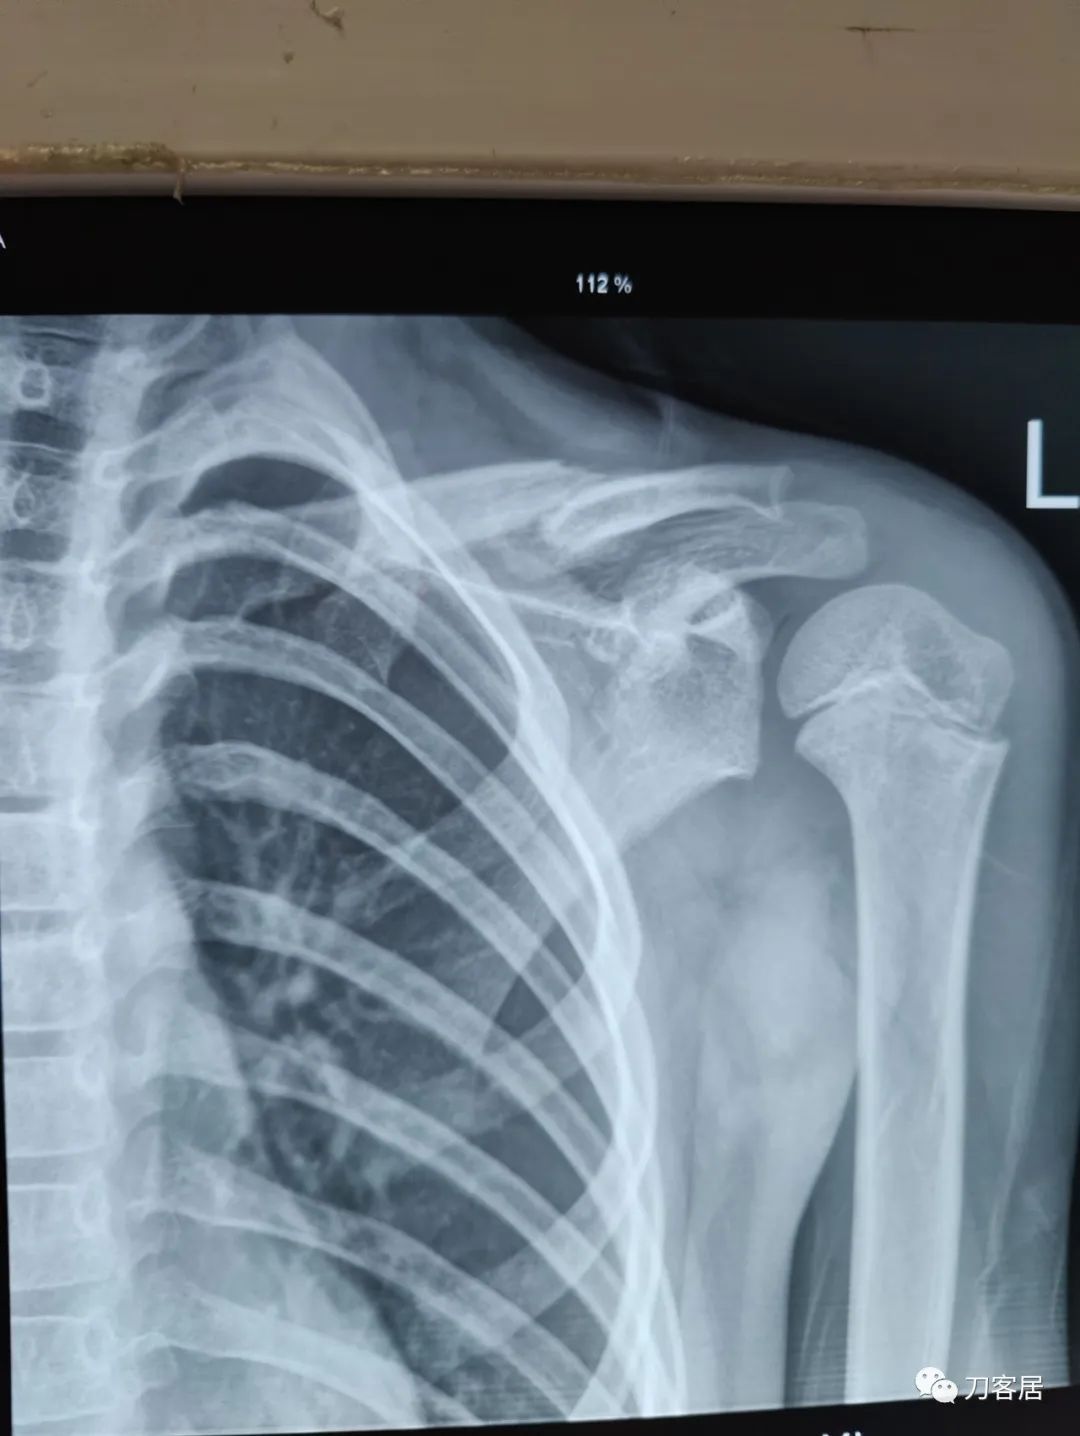

Figure 6-7 Significantly overlapped midshaft clavicle fracture in a teenager. We warn patients that the resulting callus may be the size of a walnut (or even an egg in a teenager). With time, most fractures remodel nicely.图 6-7 青少年明显重叠的中段锁骨骨折。我们应该告知患者,由此产生的骨痂组织可能有核桃大小(有的可能有鸡蛋大小)。随着时间的推移,大多数骨折都能很好地重塑。

Although x-rays of a fracture healing in bayonet opposition may frighten the parents, studies have shown that a significant amount of angulation and overlap can be accepted. Once the fracture is non-tender and there is radiographic healing, the patient may slowly return to sports. Final x-rays are usually obtained at 4-6 weeks after injury; if there are concerns of a developing non-union, longer follow-up becomes necessary.

当采用非手术方法时,骨折固定 4-6 周,另外6周内避免碰撞运动。与大多数简单的损伤一样,一半的治疗包括对患儿父母进行正常骨折愈合过程的教育。在骨折愈合(骨痂)时可能会出现难看的包块,并且在重塑过程中可能会持续一年(我们应该告诉患儿父母,包块可能有核桃或鸡蛋那么大(图 6-7)。